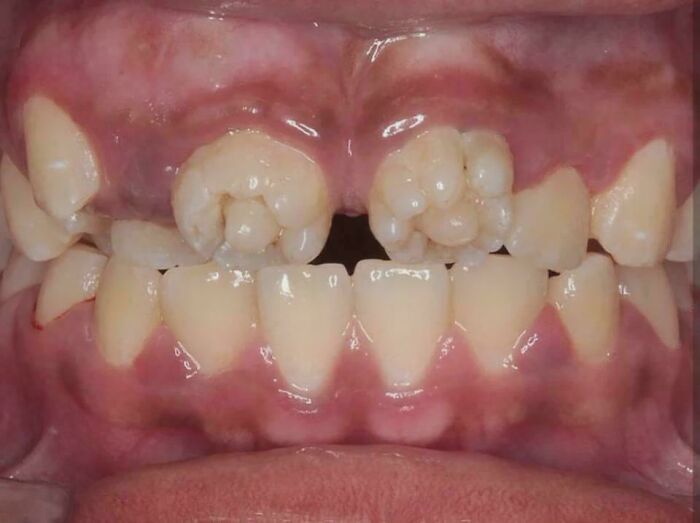

These Are Mulberry Molars, Which Are Associated With Congenital Syphilis